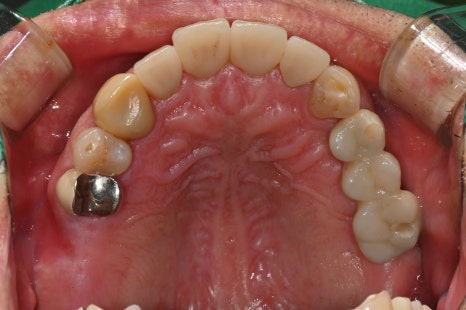

임플란트 수술 직후 X-ray 및 수술 후 구강 내 모습

⚙️ 어금니 임플란트 보철까지 완성

🖼️ 어금니 임플란트 보철 완성 사진

디지털 스캔으로 미리 설계된 임플란트 보철물 / 구강 내 실제 setting 된 모습